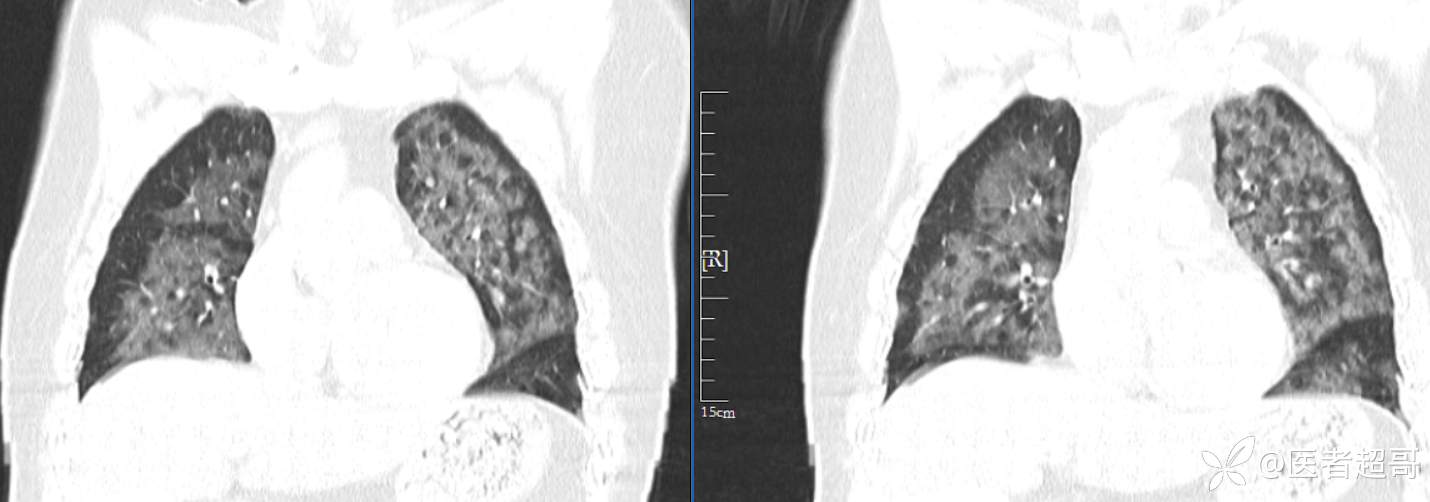

【影诊笔记574】胸痛就诊检查,发现双肺多发高密度,请赏析!

患者性别:女

患者年龄:47岁

主诉:胸痛就诊

简要病史:因“胸痛就诊”,行冠脉CTA检查,数小时后出现高热,伴畏寒寒战、气喘,暗红色泡沫样痰。

急性肺水肿 (17)